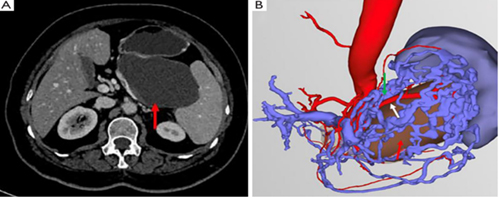

术前CT扫描和三维重建:

(A) 术前CT显示胰体尾部囊性病变(红色箭头),与脾血管毗邻关系密切;

(B)三维重建显示肿瘤与脾血管之间边界模糊(绿色箭头:脾静脉;白色箭头:脾动脉;红色箭头:胰尾病变)。